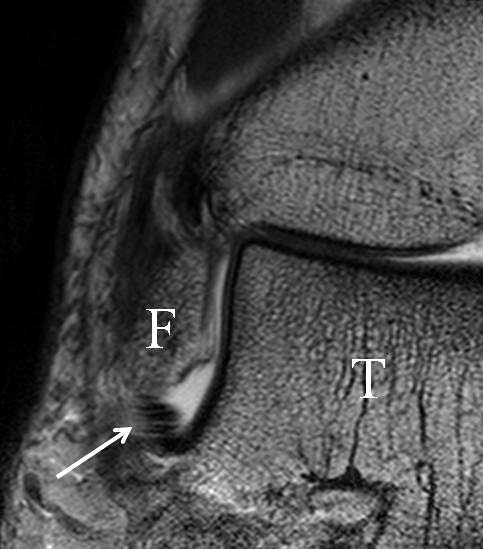

Bezogen auf die Transversalebene verläuft die Syndesmose ca. 30° schräg cranio-caudal anguliert (Abb. 15 a). Häufig lassen sich drei Hauptfaszikel differenzieren: das kürzeste superiore, das stärkste mittlere und das längste kaudale Faserbündel. Ein akzessorisches Bündel, das anteriore-inferiore, tibiofibulare Ligament (AITFL) oder auch Bassett-Ligament wird in 80-94% der Patienten nachgewiesen 8. Dies weist einen unmittelbaren Bezug zur anterolateralen Talusschulter auf (Abb. 17). In Kombination mit einer Außenbandinstabilität und konsekutivem, talarem Vorschub kann dieses zu einem Impingement an der anterolateralen Taluskante führen mit nachfolgender chondraler oder osteochondraler Läsion.

Jedoch findet man sich auch hier mit dem Problem der in den Standard-Projektionen schräg verlaufenden Syndesmose konfrontiert. Der oligofaszikuläre Aspekt der vorderen Syndesmose kann in der axialen Schnittebene eine zum Verwechseln ähnliche Morphologie wie eine Ruptur aufweisen (Abb. 15 b und c). Doppelangulierte Schnitte entlang der Achse (schräg koronar/schräg sagittal) lassen hingegen eine eindeutige Beurteilung der Bandstrukturen zu (Abb. 16) und verbessern die Syndesmosendiagnostik.